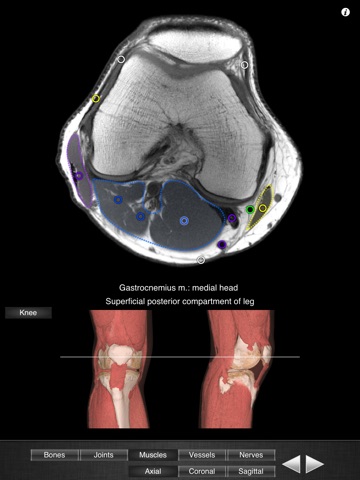

Monster Anatomy - Knee is the free version of Monster Anatomy - Lower limb, an interactive lower limb radiology atlas presented at the 2009 Radiological Society of North America annual meeting. It only contains knee images. The application was developed in the Medical Imaging Department of the University Hospital Center of Nancy, France, under the supervision of Professor Alain Blum. This application is designed for healthcare professionals (Radiologists, General Practitioners, Orthopedists, Surgeons, Physiotherapists among others) as well for students, as a reference and learning tool. It contains 82 contiguous knee MR slices (4-5 mm thickness) in the three anatomical planes. Features: - Intuitive navigation with multiple shortcuts. - Fluid display of images in the three anatomical planes. - 3D Image volume (VR) allows precise location of slice position. - Labels in accordance with the “Terminologia Anatomica" and current literature references. - The five different display modes available (bones, joints, muscles, blood vessels and nerves) facilitates label visualization. - High image quality with a zooming tool. Once the application is installed no network connection is necessary. You can download the full version on the AppStore : "Monster Anatomy - Lower limb" Dont hesitate to give some feedback on the application and to rate and comment on the AppStore! NB : Monster Anatomy - Knee is designed for trained healthcare professionals. This application is not intended as a substitute of patient/healthcare provider interaction or as a replacement of professional judgment.